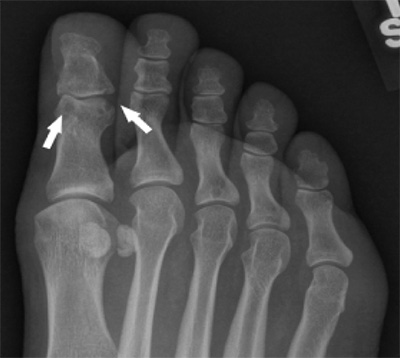

patient's foot with goutA radiograph of the patient’s foot revealed punched-out joint erosions in the big toe, features characteristic of tophaceous, erosive gout. Photo by UC San Diego Health Sciences